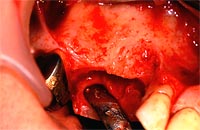

歯茎にインプラントを埋め込むのに十分な骨の厚み、幅がない場合に、当院では人工骨を移植します。

歯周組織再生療法の1つで、 歯周病等で骨が失われた部位に人工骨や自家骨(自分の骨)を移植し、骨の再生を図ります。

治療が必要な部分の歯肉を切開し、人工骨を埋め込み、再び歯肉をかぶせます。移植後、4~6カ月で骨が造成されます。

再生した骨にインプラントを埋入し、歯肉で覆います。

インプラント体と骨が結合するのを待ちます。3~6か月で結合します。

通常のインプラント手術の1次オペにあたります。